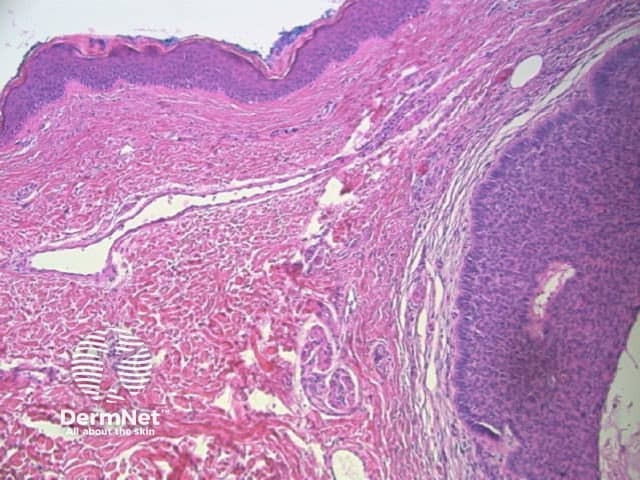

Seborrhoeic keratoses are amongst the most variable lesions on dermatoscopy, which is reflected in their protean histological appearances (Figure 15). Aside from the pseudopod pattern, any pattern or colour can be found. Flat seborrhoeic keratoses appear similar to solar lentigo on dermatoscopy. With early epidermal acanthosis thin curved lines (Figure 13) and circles become manifest, whilst with advanced acanthosis thick curved lines (Figure 14) and clods typically predominate. White clods are due to keratin under the stratum corneum. Orthokeratotic loosely laminated surface keratin appears yellow. Crypts fill with discoloured keratin and may appear various colours on dermatoscopy including brown and orange (Figure 15).

Figure 13 Figure 14 Figure 15

Figure 15a Figure 15b Figure 15c